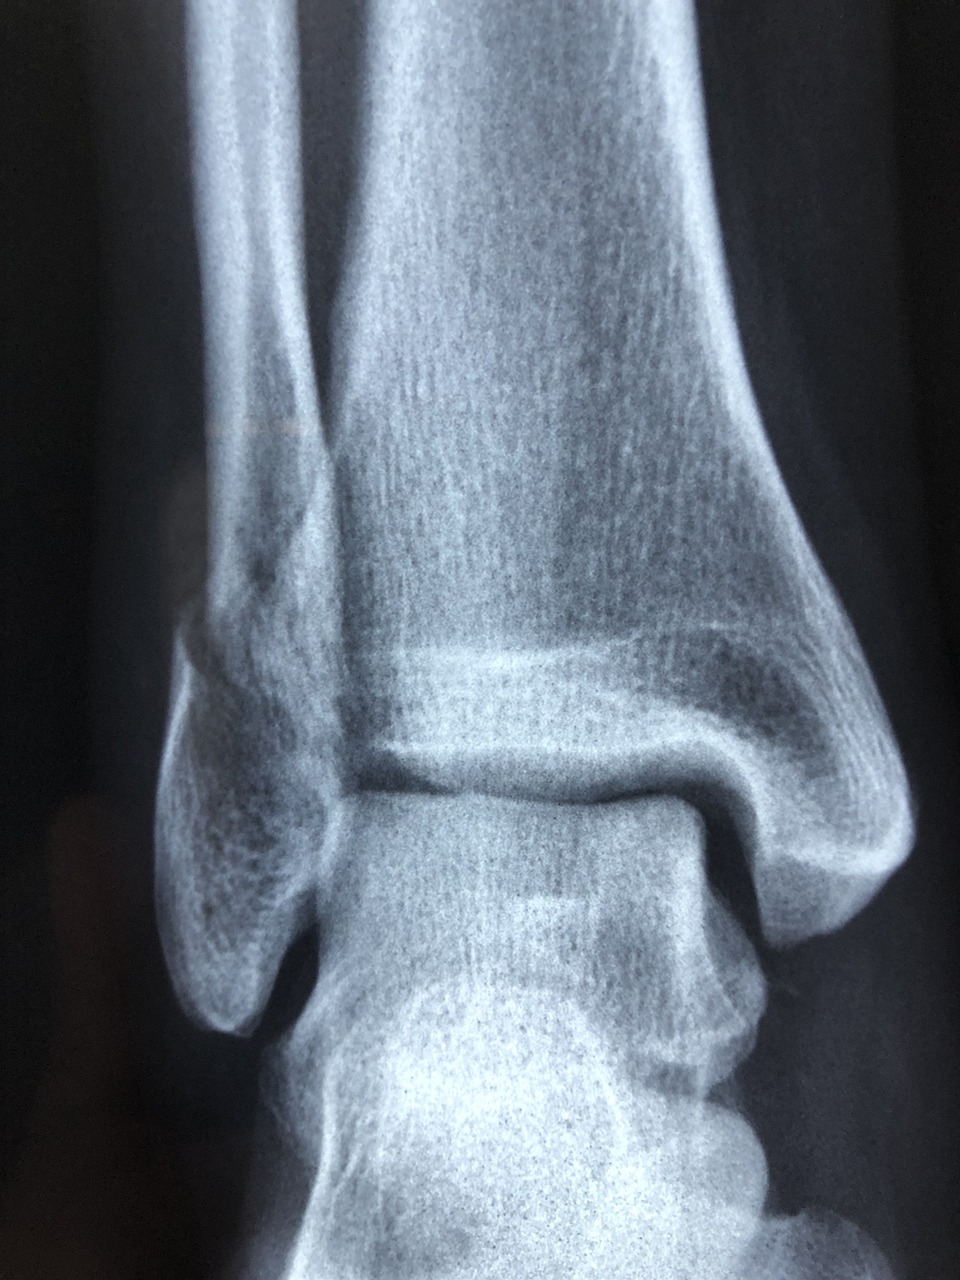

안녕하세요! 오늘은 발목인대 파열에 대해 알아보겠습니다. 특히, 발목인대의 종류와 파열 증상, 그리고 수술이 필요한 경우에 대해 자세히 설명드리겠습니다. 발목은 우리 몸에서 매우 중요한 역할을 하는 부위로, 일상생활에서 자주 사용되기 때문에 부상이 발생할 경우 적절한 대처가 필요합니다.

발목에는 여러 가지 인대가 존재하며, 이들은 각각 다른 기능을 가지고 있습니다. 주요 인대로는 다음과 같은 것들이 있습니다.

- 내측 인대 (Deltoid ligament): 발목 안쪽에 위치하며, 외부 충격으로부터 보호하는 역할을 합니다.

- 외측 인대 (Lateral ligaments): 외측에는 세 개의 주요 인대가 있으며, 각각 전거비 인대(Anterior talofibular ligament), 후거비 인대(Posterior talofibular ligament), 종아리 인대(Calcaneofibular ligament)로 나뉩니다. 이들은 주로 외측 안정성을 제공합니다.

보통 발목인대 중 전거비 인대, 후거비 인대가 파열되는 경우가 많습니다.

2. 발목인대 파열 증상

발목인대를 다쳤을 때 나타나는 증상은 다양합니다. 일반적으로 다음과 같은 증상이 나타납니다.

- 통증 : 부상의 즉시 통증이 발생하며, 특히 움직일 때 더 심해질 수 있습니다.

- 부기 : 부상 부위가 붓고 염증이 생길 수 있습니다.

- 멍 : 피부 아래 출혈로 인해 멍이 들기도 합니다.

- 움직임 제한 : 통증과 부기로 인해 정상적인 움직임이 어려워질 수 있습니다.

특히 완전한 파열(3도 염좌)의 경우에는 위와 같은 증상이 더욱 심하게 나타나며, 걷거나 서는 것이 불가능할 정도로 고통스러울 수 있습니다.